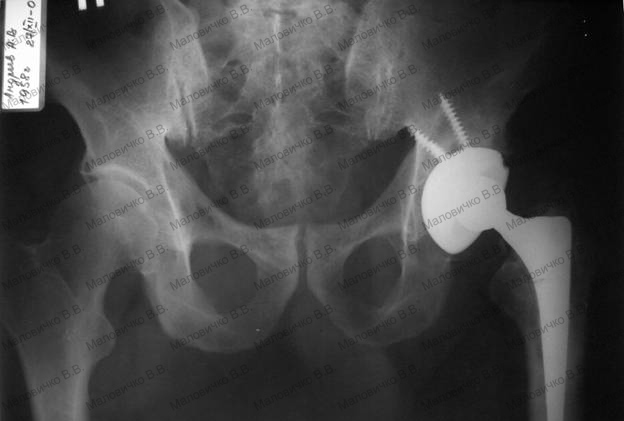

Иллюстрации и снимки, связанные с остеопенией шейки бедра